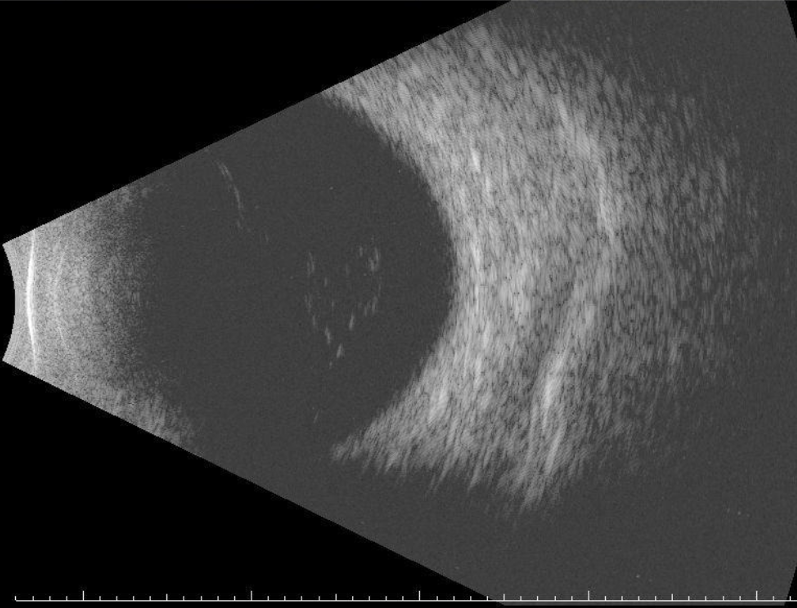

• Ophthalmic ultrasound showed mild vitreous opacities and total posterior vitreous detachment bilaterally without retinal or choroid thickening (Figure 2).

Figure 2. Ophthalmic ultrasound of left eye on our initial evaluation did not suggest endophthalmitis or concurrent retinal detachment.